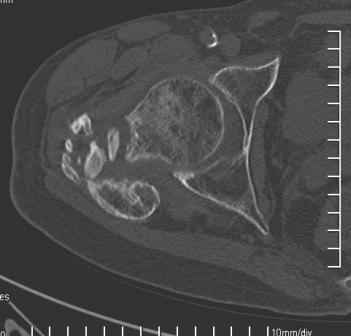

Больной Н. 44 года травма 1,5 года назад июнь 2008 года чрез-под вертельный перелом правого бедра. Во время лечения у больного развился алк. делирий, проводилось консервативное лечение перелома.

Беспокоят боли, укорочение конечности.Укорочение 3 см. Ногу поднимает, сгибание ограничено, ротационные движения в полном объеме.На КТ перелом сросся за счет костной мозоли.Что делать?

Уважаемый Глеб, боли из-за ложного сустава шейки бедра. Сращения там нет.

Уважаемый Глеб! Укорочение наверное побольше, да и наружно-ротационная установка скорее всего присутствует. Суставная щель прекрасная, головка живее всех живых. Ратую за подвертельную с латерализацией: исключает нарушение механической оси («исключает вальгус в коленe»), максимально удлиняет без натяжения m.iliacus. Для иллюстрации остеотомия-переделка (слава богу не автопеределка) у мужчины 65 лет.